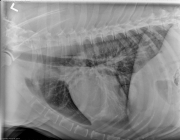

There is also an opacity in the right hemithorax which is adjacent to the right body wall. It is seen best on the d/v and left lateral projections. A second opacity is visible overlying the caudal lungs on this projection, and is not visible on the v/d.

The thoracic nodule was difficult to localize on the standard projections. Visibility of an extrapleural sign depends on catching it perpendicular to the x-ray beam. Centering over the lesion and collimating can help, as can rotating the dog to either side.

376632_9yr-K9-MC-X-ROTT_5

This radiograph was taken centered over the pulmonary lesion. It shows the rib has lytic and expansile components, and that the rib mass is protruding into the thorax. This is most likely metastatic disease from the osteosarcoma. It is a very nice example of an extrapleural sign, where the mass has a broad base and extends to the pleural surface.